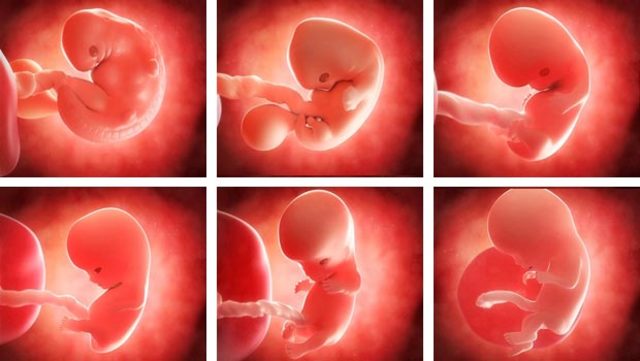

• 2 Semana (Embrión)

2 Semana (Embrión)

*Las células nerviosas que se están creando formarán el cerebro y el tubo neural.

*La masa embrionaria se dobla para formar lo que será la cabeza (parte superior) y el tronco (parte inferior)

• 3 Semana

3 Semana

*Se forma lo que será el corazón, a través de una reacción en cadena de una célula que se contrae y hará latir a las demás a su alrededor.

*El embrión tiene un conato de sistema nervioso y corazón.

• 8 Semanas (Feto)

8 Semanas (Feto)